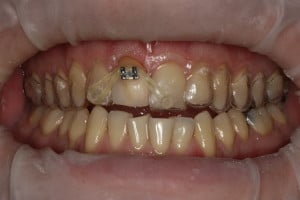

Przykład ekstruzji ortodontycznej za pomocą płytki termoformowalnej i zameczka ortodontycznego: